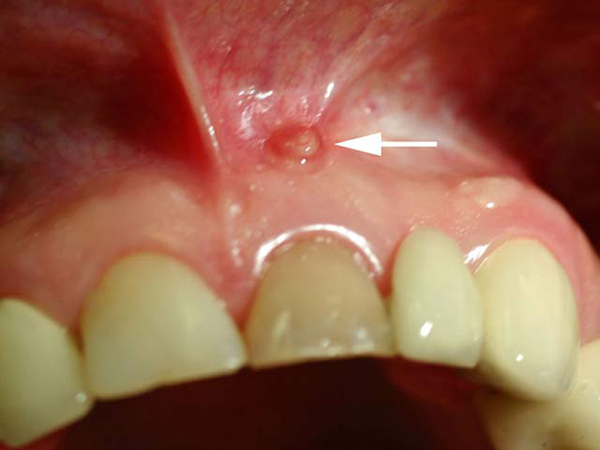

Ситуация усугубляется образованием нескольких нагноений в очаге воспаления, поражающих не только дёсны, но и мягкие ткани полости рта. При запущенном состоянии часто возникают свищи, что приводит к образованию гранулём.

Если гранулёма вскрывается, её место занимает бороздка, которая со временем превращается в грубый рубец. Гранулирующий периодонтит диагностируется с помощью микроскопического исследования образца поражённой ткани.

• Гранулирующий. Сопровождается слабыми болями или неприятными ощущениями. В области пораженного зуба может возникать чувство распирания, тяжести, накусывание может быть неприятным. В десне рядом с больным зубом появляется свищ, через который выходит гной и грануляционная ткань. Десна может иметь измененную окраску и структуру, пальпация может быть болезненной. Лимфатические узлы могут увеличиваться и становиться чувствительными.

На этой стадии обострения появляется отек десны около больного зуба. В конечном итоге может произойти вскрытие мягких тканей и образование свища, через который выходит гной. При достаточном оттоке гнойных масс обострение может утихнуть. Преждевременное закрытие свища приводит к усилению воспалительного процесса.

Эта форма требует микроскопического исследования. Наблюдается утолщение над верхней частью зубного корня и изменения поверхности периодонта, такие как неровность и искривление. Грануляционная ткань постепенно увеличивается, что приводит к рассасыванию костной ткани и образованию гнойных очагов. Это может вызвать свищи, а в редких случаях грануляция затрагивает мягкие ткани вокруг воспаления.